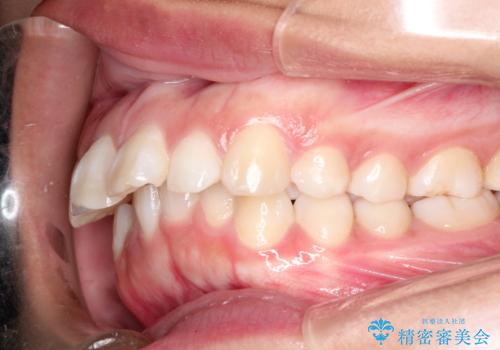

- 出っ歯を主訴に来院されました。

下の歯並びに対して、上の歯が全体的に前方に位置している状態でした。

抜歯をすることでしっかり前歯を後方に移動させて、引っ込めることができました。